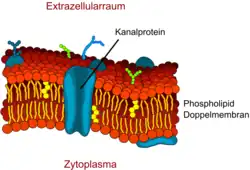

Kanalvermittelte Permeabilität

Für die Diffusion von Wasser befinden sich in der Zellmembran spezielle hydrophile Kanal-Proteine, die Aquaporine. Während nicht-zerebrale Endothelien sehr oft Aquaporin-1 (AQP1) exprimieren, ist dieses Gen an der Blut-Hirn-Schranke inaktiviert. Die Anwesenheit der Astrozyten inhibiert die AQP1-Expression.[116] Die spezialisierten zerebralen Endothelien exprimieren im Wesentlichen Aquaporin-4 (AQP4)[117] und Aquaporin-9 (AQP9).

Über die Aquaporine wird der Wasserhaushalt des Gehirns reguliert. Sie ermöglichen eine hohe Kapazität für die Diffusion von Wasser in beide Richtungen, jeweils dem osmotischen Gradienten folgend.[118] Für Glycerin, Harnstoff und Monocarboxylate[119] bilden die Aquaglyceroporine eigene Kanäle in der Plasmamembran. An der Blut-Hirn-Schranke ist dies im Wesentlichen das auch für den Wassertransport zuständige Aquaporin-9.[119]

Kanäle sind für den Molekültransport wesentlich schneller als Transporter. Durch Spannungsimpulse oder interagierende Hormone und andere Einflussfaktoren können die Ionenkanäle aktiviert oder deaktiviert werden (Gating).[99]